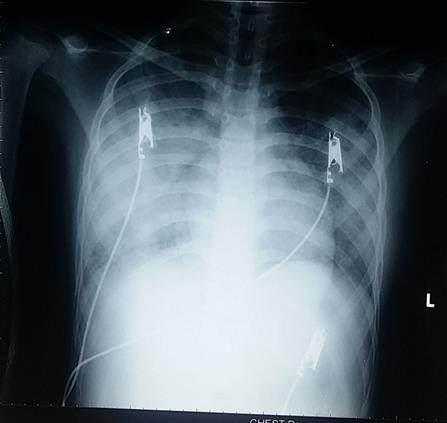

Tại BV Nhi Đồng 2, các xét nghiệm ban đầu cho thấy bé gái có tình trạng viêm phổi nặng với XQ ngực thâm nhiễm lan tỏa 2 phế trường nhưng các xét nghiệm nhiễm trùng không tăng nhiều. Nghi ngờ bệnh nhi mắc hội chứng xuất huyết phế nang lan tỏa, nên các BS đã cho bệnh nhân chụp CTscan ngực có cản quang và tiến hành nội soi phế quản bằng ống soi mềm.

Trên kết quả CTscan ngực cản quang cũng ghi nhận hình ảnh kính mờ rải rác 2 phế trường, phù hợp với chẩn đoán trên. Cuối cùng, bệnh nhân được tiến hành sinh thiết phổi bằng nội soi lồng ngực để chẩn đoán xác định.